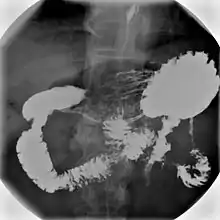

An upper gastrointestinal series, also called a barium meal, is a series of radiographs used to examine the gastrointestinal tract for abnormalities. A contrast medium, usually a radiocontrast agent such as barium sulfate mixed with water, is ingested or instilled into the gastrointestinal tract, and X-rays are used to create radiographs of the regions of interest. The barium enhances the visibility of the relevant parts of the gastrointestinal tract by coating the inside wall of the tract and appearing white on the film. This in combination with other plain radiographs allows for the imaging of parts of the upper gastrointestinal tract such as the pharynx, larynx, esophagus, stomach, and small intestine such that the inside wall lining, size, shape, contour, and patency are visible to the examiner. With fluoroscopy, it is also possible to visualize the functional movement of examined organs such as swallowing, peristalsis, or sphincter closure. Depending on the organs to be examined, barium radiographs can be classified into "barium swallow", "barium meal", "barium follow-through", and "enteroclysis" ("small bowel enema"). To further enhance the quality of images, air or gas is sometimes introduced into the gastrointestinal tract in addition to barium, and this procedure is called double-contrast imaging. In this case the gas is referred to as the negative contrast medium. Traditionally the images produced with barium contrast are made with plain-film radiography, but computed tomography is also used in combination with barium contrast, in which case the procedure is called "CT enterography".[1]

Various types of barium X-ray examinations are used to examine different parts of the gastrointestinal tract. These include barium swallow, barium meal, barium follow-through, and barium enema.[2] The barium swallow, barium meal, and barium follow-through are together also called an upper gastrointestinal series (or study), whereas the barium enema is called a lower gastrointestinal series (or study).[3] In upper gastrointestinal series examinations, the barium sulfate is mixed with water and swallowed orally, whereas in the lower gastrointestinal series (barium enema), the barium contrast agent is administered as an enema through a small tube inserted into the rectum.[2]

- Barium meal examinations are used to study the lower esophagus, stomach and duodenum.[2]

Barium meal and barium follow-through

For barium meal or barium follow-through examinations, a 6-hour period of fasting is observed prior to the studies.[10] Barium is administered orally, sometimes mixed with diatrizoic acid to reduce transit time in the bowel. Metoclopramide is sometimes also added to the mixture to enhance gastric emptying. X-ray images are then taken in a supine position at intervals of 20–30 minutes. Real-time fluoroscopy is used to assess bowel motility. The radiologist may press or palpate the abdomen during images to separate intestinal loops. The total time necessary for the test depends on the speed of bowel motility or transit time and may vary between 1 and 3 hours.[15][13]